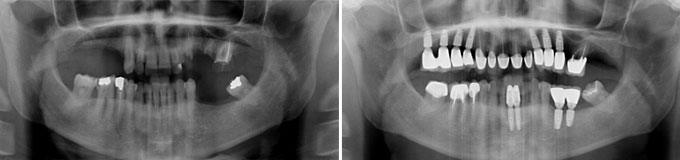

J’ai une maladie des gencives et mes dents tombent les une après les autres, je refuse un appareil que je serais obligé d’enlever

Solution : on va traiter les dents qui sont récupérables et remplacer les autres par des implants.

Implants multiples pour éviter les bridges et redonner des dents individuelles au patient avec traitement d’une maladie parodontale.

Implants multiples pour éviter les bridges et redonner des dents individuelles au patient. État final.